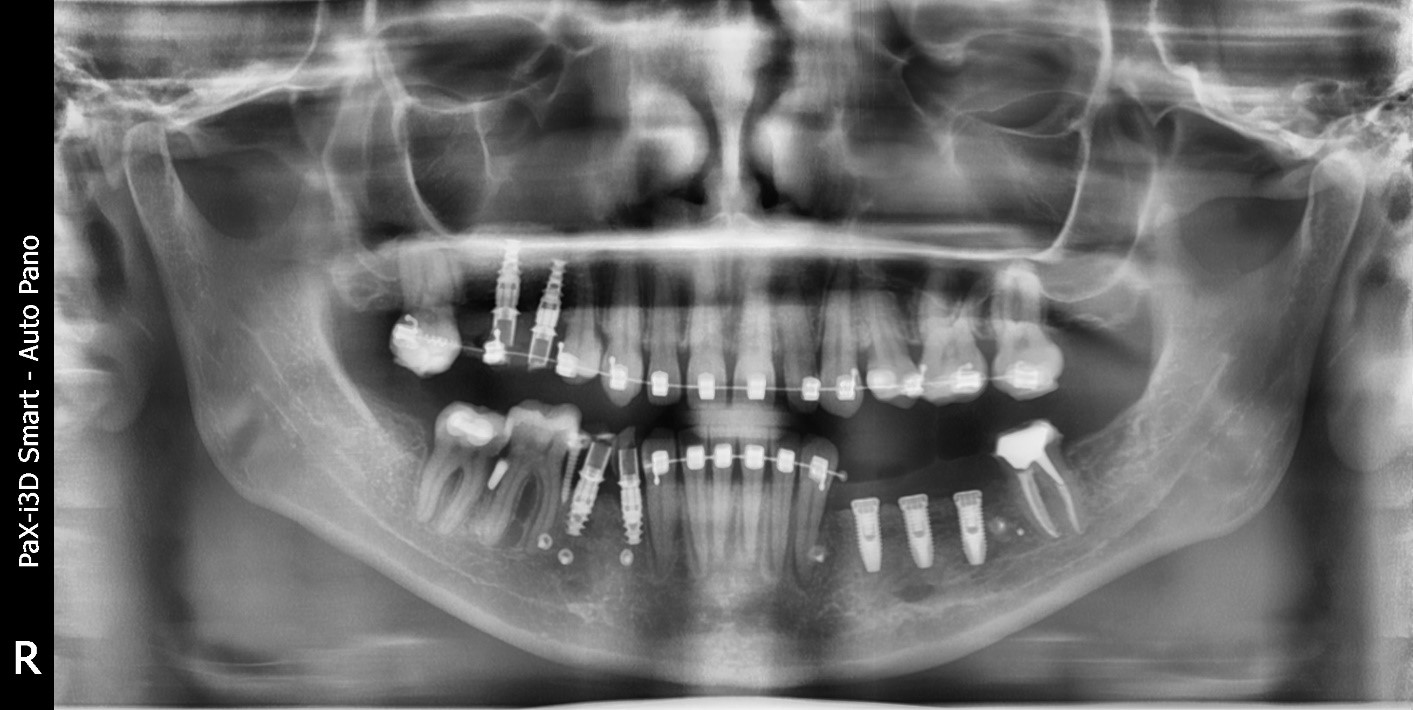

Снимок ротовой полости того же пациента, о котором мы говорили вначале. Нижняя челюсть, справа и слева от оставшихся зубов проложена смесь костной стружки. Она закреплена каркасом из титановой сетки, которая, в свою очередь, закреплена титановыми винтами.

Мы начали с того, что ортодонт зафиксировал зубы. На это потребовалось около двух месяцев, движение зубов остановилось, мы смогли перейти к остеопластике. Сама операция прошла вполне штатно. И потом мы подождали около полугода, чтобы кость сформировалась и… Вы думаете, мы поставили импланты? Ничего подобного: мы снова поставили брекеты, чтобы она могла доносить их положенные два-три месяца.

Кстати, после костной пластики зубы двигаются немного быстрее: кость становится менее однородной, размягчается, сопротивление меньше. Когда зубы встали на место, мы смогли перейти к обычным процедурам: имплантация, ожидание, потом — протезирование. В итоге у девушки появились прекрасные импланты и коронки.

Та же девушка с брекетами после костной пластики и имплантации. Видно, что с левой стороны кость выровнялась. Настолько, что была возможность поставить импланты потолще. С правой стороны костной пластики не было. Кость была тонкая, но всё же мы пришли к выводу, что показаний к пластике нет. Но там поставили импланты тоньше. Когда они прижились, толщина уже не имеет значения, они так же хорошо держат нагрузку.

Правда, общее время ношения брекетов увеличилось на семь-восемь месяцев: быстрее кость, к сожалению, не приживается. Точнее, время можно сократить месяца на два, если принимать специальные препараты. Но в России они не сертифицированы. Так что, если хочется побыстрее и нет проблем с деньгами и временем, можно на время уехать куда-нибудь за границу, где с сертификатами всё в порядке. В нынешней ситуации, однако, это скорее из области фантастики.

В нашем случае девушке требовалась костная пластика под три импланта. Мы делали с титановой сеткой. Это было около трёх лет назад, операция обошлась ей в общей сложности в 110 тысяч рублей. Сегодня это стоило бы около 200 тысяч.